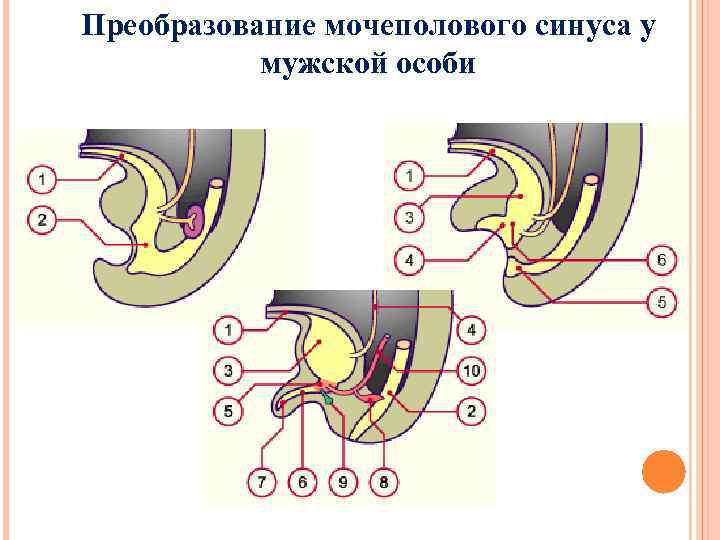

Преобразование мочеполового синуса у мужской особи

Преобразование мочеполового синуса у мужской особи